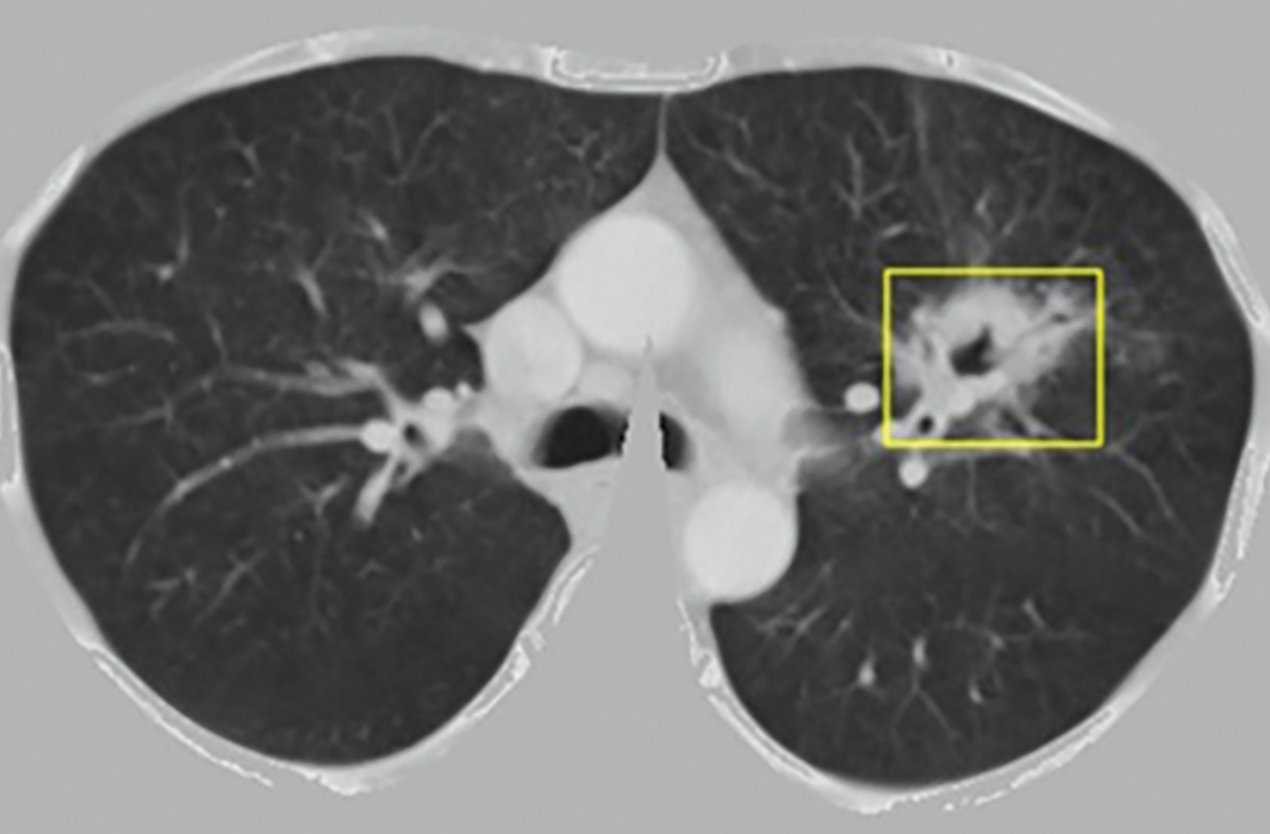

Hình ảnh kết quả của mô hình nhận dạng nốt, khối u phổi trên ảnh cắt lớp vi tính. Nguồn: TS Trần Giang Sơn

Do đó, trong đề tài “Xây dựng hệ thống nhận dạng ảnh y tế hỗ trợ chẩn đoán bệnh ung thư phổi dựa trên học máy và tính toán hiệu năng cao” của Viện Hàn lâm KH&CN VN giao, nhóm nghiên cứu đề xuất xây dựng một hệ thống phần mềm mẫu nhận dạng ảnh y tế nhằm hỗ trợ bác sĩ trong việc chẩn đoán bệnh ung thư phổi và tập trung vào ung thư phổi không tế bào nhỏ (dạng ung thư chiếm khoảng 85% các ca bệnh). Sau hai năm thực hiện, TS Trần Giang Sơn và nhóm tác giả từ Đại học Việt – Pháp (USTH) phối hợp với Bệnh viện K đã xây dựng thành công mô hình phát hiện và nhận dạng vị trí, kích thước các nốt, khối u phổi trên ảnh chụp cắt lớp vi tính, đồng thời xây dựng thành công mô hình phân loại các nốt, khối u phổi trên ảnh chụp chụp cắt lớp vi tính là lành tính hay ác tính. Ngoài ra, nhóm tác giả cũng xây dựng được bộ dữ liệu ảnh chụp cắt lớp vi tính mẫu về ung thư phổi ở Việt Nam. Các sản phẩm cụ thể gồm: Hệ thống hỗ trợ chẩn đoán ung thư phổi LungCancer Care; công cụ gán nhãn mã nguồn mở LungTumorMarker; bộ dữ liệu mẫu về ung thư phổi tại Việt Nam.